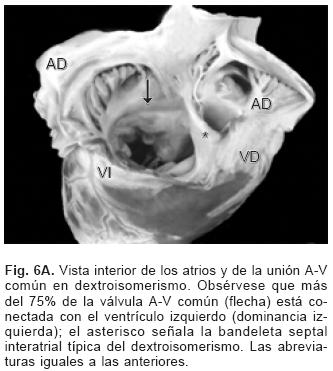

En los setenta corazones estudiados el situs atrial que predominó fue el solitus seguido de dextroisomerismo, inversus y levoisomerismo (Figs. 2A y 2B). La conexión A–V predominante fue concordante seguida de la doble entrada a ventrículo único, doble entrada a ventrículo derecho, ambigua y discordante (Tabla I). Los tipos de conexión ventriculoarterial se consignan en la Tabla II.

De los sesenta y cinco corazones con válvula común en veinticinco se determinaron los tipos de la clasificación de Rastelli que fueron los siguientes: en once (44%) las valvas anterosuperiores derecha e izquierda se insertaron a través de sus cuerdas tendinosas sobre la cresta del tabique ventricular y la CIV se ubicó en los espacios intercordales (tipo A de Rastelli) (Figs. 1A y 5A). En un espécimen las valvas anterosu–periores izquierda (valva puente) y derecha se insertaron sobre la cara derecha del tabique ventricular por debajo de su cresta (Fig. 5B) y en otro dicha inserción se hizo en la parte superior del cuerpo de la trabécula septomarginal (Fig. 5C). En ocho corazones (32%) la inserción de esas valvas se estableció en un músculo papilar situado en la unión del tabique ventricular con la pared libre del ventrículo derecho y la valva anterosuperior izquierda pasó como puente por encima de la CIV (tipo B de Rastelli) (Figs. 1B y 5D) y en seis corazones (24%) la inserción de las valvas anterosuperior izquierda (valva puente) y derecha se insertaron en un músculo papilar de la pared libre del ventrículo derecho y esta valva se ubicó por encima de la CIV (tipo C de Rastelli) (Figs. 1C y 5E). En los cuarenta corazones restantes no fue posible determinar los tipos de Rastelli debido a que treinta y tres de ellos presentaron doble entrada ventricular (Fig. 6A) dos tuvieron modificaciones anatómicas generadas por la cirugía y cinco por presentar mutilaciones realizadas durante la necropsia. Los cinco especímenes con dos válvulas separadas tuvieron estructura trifoliada dentro de la unión A–V común (Figs. 3B y 6B); la válvula A–V izquierda mostró una valva lateral y dos septales anterior y posterior unidas a la cresta del tabique ventricular, lo que obliteró la CIV (Fig. 6C). La válvula A–V derecha mostró una valva septal displásica, una anterior y una posterior (Figs. 3B y 6B).

El DSA–V puede presentarse en cualquier situs lo que es más frecuente dentro de la población con dextroisomerismo en la que los corazones muestran múltiple asociación de defectos intracardíacos. Otras cardiopatías congénitas asociadas son la estenosis pulmonar, doble salida de ventrículo derecho, Tetralogía de Fallot, transposición de las grandes arterias, doble entrada ventricular.